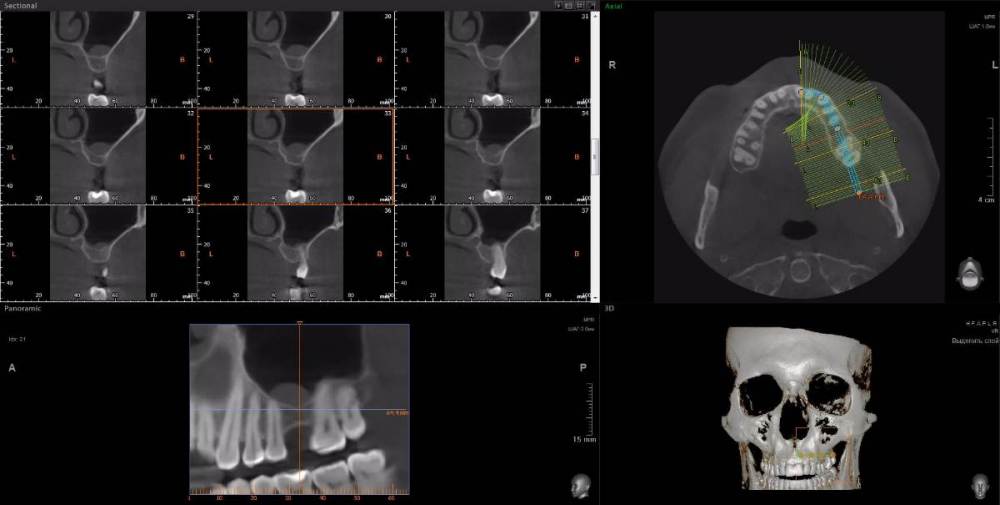

peter42 Опубликовано 10 декабря, 2021 Поделиться Опубликовано 10 декабря, 2021 (изменено) Доброго времени суток уважаемые доктора! Несколько лет назад (более 15) у меня был пульпит 6-го зуба (вверху слева), позже была безуспешная попытка его перелечить, в результате которой, зуб раскололся пополам и его пришлось удалить. Перелечивать зуб я пытался по тому, что после употреблении холодной пищи (или жидкости) у меня примерно через сутки начинались боли сначала в челюсти, в области левой пазухи в проекции над зубом, а спустя некоторое время болела уже вся голова. Также ощущалось чувство давления, набухания в этой области, усиливалась заложенность носа с левой стороны. При этом припухлости десны, выделений из носа (гной, слизь) не было, и сейчас тоже нет. Через год после удаления зуба, я был на приеме у парадонтолога, который направил меня на рентген (панорамный снимок), взглянув на снимок, он заметил, что корень зуба был удален не полностью - в челюсти остался корень. Позже этот корень мне благополучно удалили (тот же стоматолог- хирург). Однако уже прошло много лет, а все осталось как и до удаления - стоит мне снова простудиться или просто поесть мороженного (выпить даже не очень холодной воды), то через некоторое время (около суток) опять начинаются боли в верхней челюсти, болит голова, пенталгин и тот не всегда хорошо помогает снять боль. По рекомендации знакомых я обращался к другому стоматологу, который меня направил на" 3Д" КТ зубов. Посмотрев снимки он заключил, что в левой пазухе у меня тоже киста, и что это проявление гайморита. ЛОР посмотрев КТ сказал, что это кисты и они очень мелкие (ретенционные) имеют «зубную» природу, в связи с чем, давать такую болевую симптоматику не могут. Также я ходил на консультацию к неврологу, который по характеру боли (ноющая, не резкая, возникающая и прекращающаяся постепенно, присутствует ночью, не болит лицо) заключил, что причина скорее всего в зубах или в пазухе — круг замкнулся. На сегодня вся симптоматика сохраняется (боль, заложенность носа), болит в районе зуба 2,7 и 6-го удаленного зуба, сам склоняюсь, что болит все таки зуб 2,7 По совету знакомого почитал Ваш форум, сделал свежее «3Д» КТ зубов и пазух на аппарате «Ватек» в «Пикассо». Прошу Вас посмотреть КТ и дать совет, что мне предпринять, есть ли у меня стоматологические проблемы, вызывающие боли и другие симптомы? https://drive.google.com/drive/folders/1GXwLnOF5bPR5duemJODcfdSJHJyQORxC?usp=sharing Изменено 10 декабря, 2021 пользователем peter42 Ссылка на комментарий

peter42 Опубликовано 11 декабря, 2021 Автор Поделиться Опубликовано 11 декабря, 2021 Спасибо за ответ. Я в апреле оперировался у очень хорошего ЛОРа в Москве (перегородка, раковины), ему об этой проблеме тоже говорил, но он считает, что эта киста маленькая и "клинически не значима" (дословно) и трогать ее смысла нет. Интересно, что справа тоже есть кисты, но там нет такой проблемы. Кстати справа мне в 2011 г. кисту удаляли, но она снова выросла. В описании КТ рентгенолог указал на кариес в 2,7, как считаете, может ли он быть причиной пульпита и болей? Ссылка на комментарий

peter42 Опубликовано 28 декабря, 2021 Автор Поделиться Опубликовано 28 декабря, 2021 А кариес нужно на 2,7 лечить? Мой стоматолог утверждает, что он небольшой и надо наблюдать Ссылка на комментарий